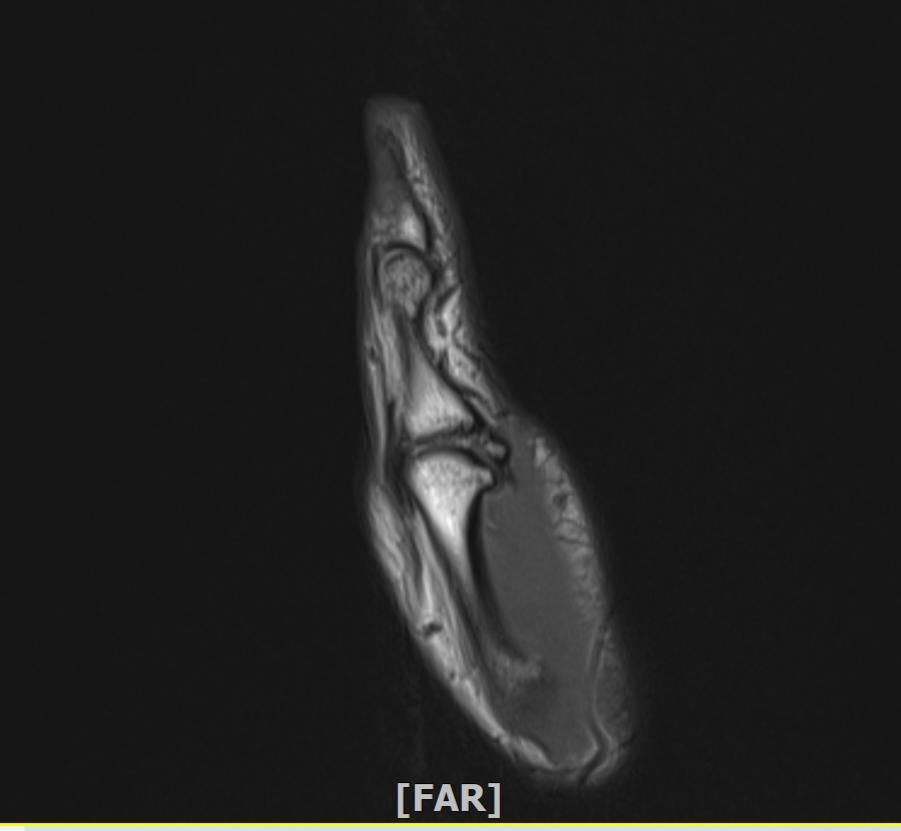

mri 엄지손가락 미세골절 여부확인

공구에 왼손이 말려서 엄지를 다쳤습니다 응급실에서 부목고정 조치후 이틀후 mri촬영 하였습니다.

엄지손가락 뼈가 자주 욱씬거리는데 미세골절 여부 확인 부탁드립니다.

• 4번 째 사진

우선 현재로썬 MRI 사진으론 정확한 판단을 하긴 어렵지만 주변 연부조직의 손상이 보여집니다.

다만 미세골절 같은 경우는 여러 방면의 판독이 필요하므로 정확한 판독은 병원에 내원하셔서 MRI 촬영을 한 병원에 판독지를 받으시고 전문의에 판독을 받으시길 적극 추천드립니다.

또한 미세골절 같은 경우는 통증 부위를 정확히 짚을 수 있다면 초음파 검사를 통해 확인해보시는것도 좋습니다.